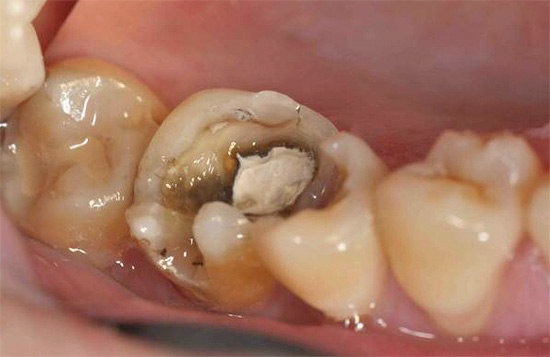

Un dente che è stato a lungo sigillato nei canali con un riempimento sigillato di alta qualità di solito non dà fastidio se non si sono verificati errori durante il trattamento. Se il vecchio sigillo cessa di soddisfare i requisiti di tenuta, o addirittura vola in pezzi, allora un dente morto inizia a ferire a causa dell'infezione nei canali già sigillati. Inoltre, durante il trattamento potrebbero essere commessi errori: un canale sigillato in modo incompleto con un'infezione rimasta al suo interno, uno strumento dentale rotto nel canale, ecc. Tutto ciò può anche causare infiammazione alla radice del dente e dolore nel tempo.

In ogni caso, se c'è un dolore al dente sotto un vecchio riempimento, dovresti consultare immediatamente un dentista, poiché questo è un segno sicuro dello sviluppo di processi patologici.